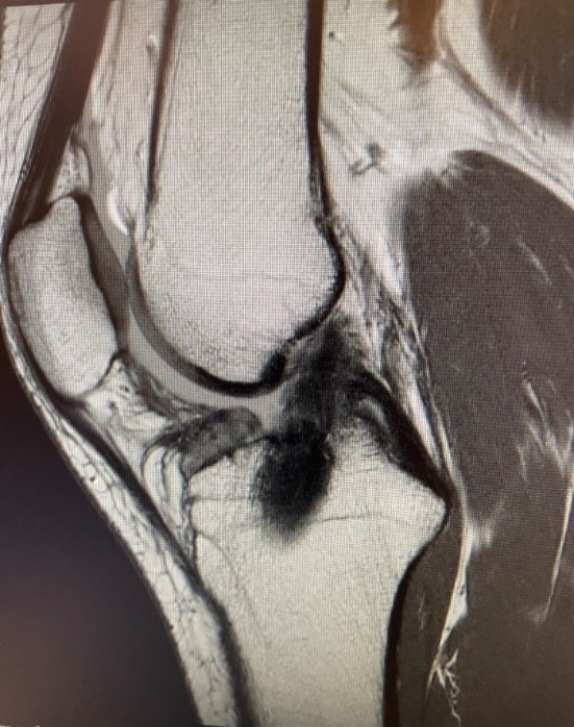

As part of her post-operative evaluation, a follow-up MRI was performed 18 months after surgery. This MRI demonstrated a robust, well-healed ACL graft (Figure 4), characterized by homogeneous low intensity signals throughout the graft construct. This corresponds to Grade I on the MRI grading scale proposed by Howell et al (Howell, Clark, and Blasier 1991)., which is indicative of a mature, well-integrated graft.

For this patient, we chose to augment the hamstring graft with BioBrace to increase graft diameter and initial strength. Female athletes, who are at greater risk of ACL re-rupture, may benefit significantly from graft augmentation to promote strength and facilitate early incorporation, potentially improving clinical outcomes. The MRI captured at 18 months post-operation depicts a robust, well-healed ACL graft, suggesting that BioBrace had fully incorporated into the remodeled graft.